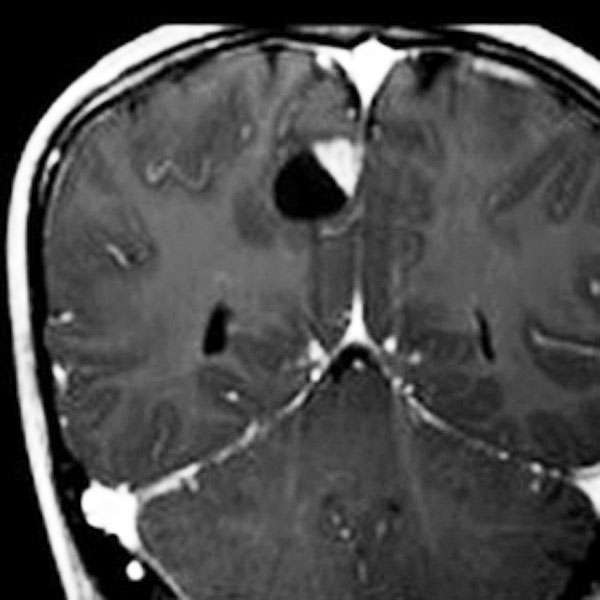

18歳で発症して,60歳まで無治療の大きな視床下部毛様細胞性星細胞腫

hypothalamic pilocytic astrocytoma

1968年 18歳の時に頭痛嘔吐で発症しました。第3脳室腫瘍と閉塞性水頭症の診断だけで,シャント手術を受けました。手術も化学療法も放射線治療もされていません。下の画像は60代で撮影されたものです。この例では,第3脳室内に増大した大きな毛様細胞性星細胞腫が,視床下部下垂体障害を出すことなく,自然経過で増大停止 growth arrest して,カチカチに固まってしまうということを教えてくれます。でも,こんなに都合よく経過観察できる例も珍しいです。

CTでは強い石灰化があります。右のT2強調画像では腫瘍は等信号,視交叉の後ろにあります。内部の低信号は石灰化です。

T1強調画像では等信号,ガドリニウム増強でごく一部がまだらに増強されます。